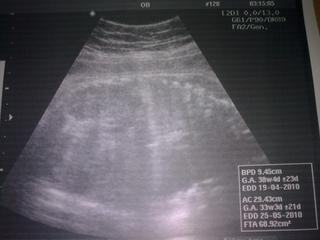

Ted jsem dorazila z pracáku, poradny a sociálk.y Poradna dopadla dobře, dělala stěry na streptokoka, brali odběry ... nechala jsem si udělat za 100,- UTZ, maličká je opět potvrzená jako ONA. Odhadem má 2600g, a máme větší hlavičku (myslím že to tady už řešila medan nebo kdo). Prý ji máme velkou jako strarosta 😀 Tak snad je vše ok. Napsala mi další Mg, že ho ještě týden mám brát a pak vysadit. V pondělí další poradna už s monitorem.